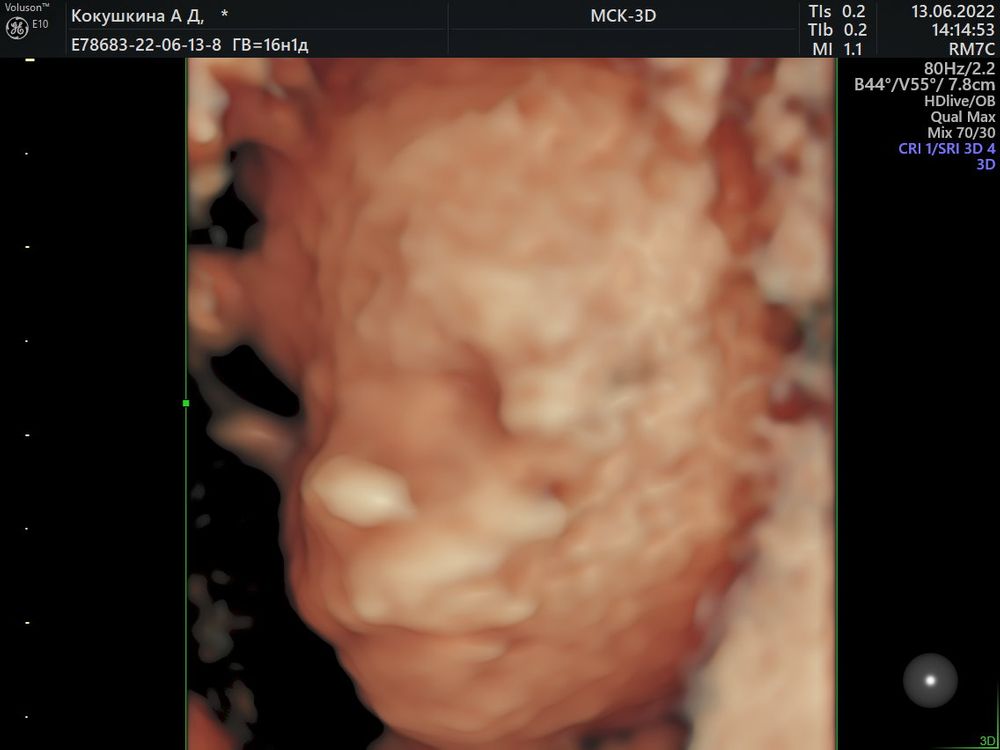

Узнали пол малыша в 16-17 недель🥰

На первом и правда не видно половой бугорок.

Поздравляюююю😍😍😍🌸🌸🌸 это уже 3 пост, где пишут, что по первому скринингу возможно девочка, по второму уже точно мальчик😂 у меня тоже так получилось🤗🤗🤗